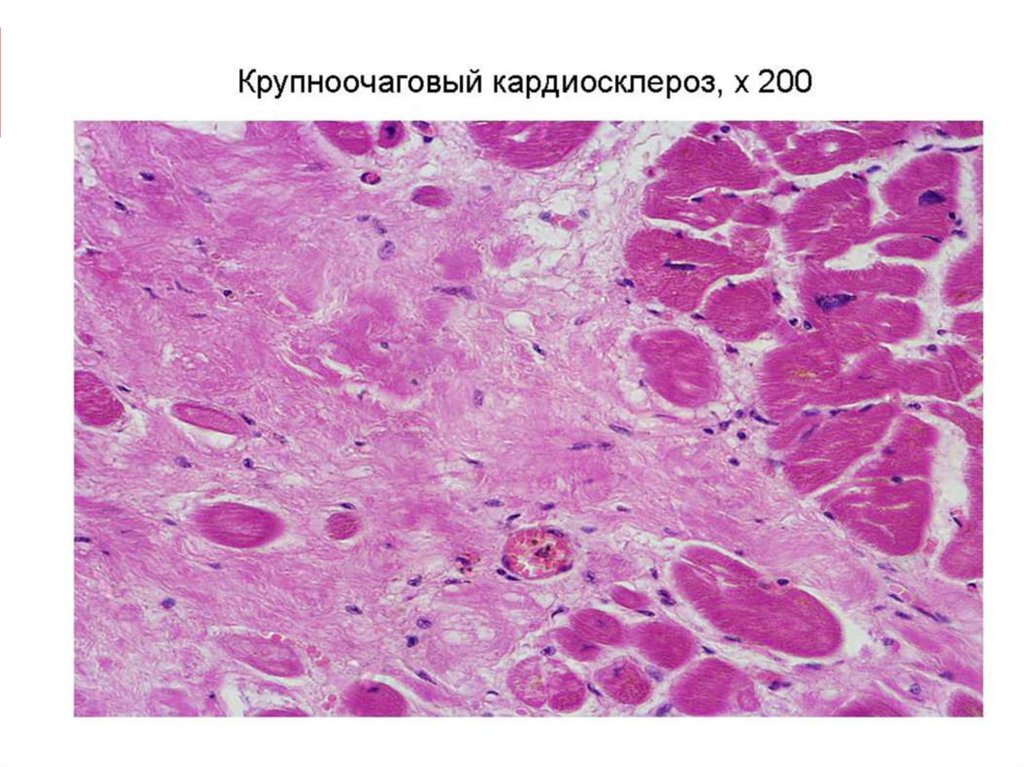

Межуточный миокардит: гистологические исследования

Раздел: Идеи и советы